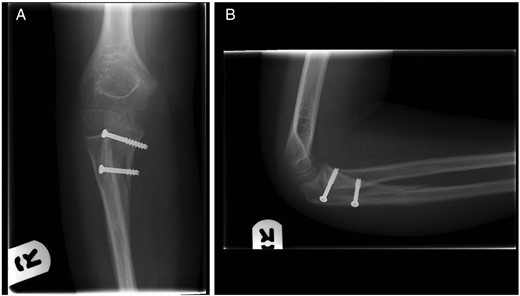

An 8-year-old boy presented with an extension injury to his dominant right elbow, sustained as a result of a fall on a dry ski slope. Examination demonstrated tenderness and swelling of the right proximal forearm with a reduced range of motion. There was no neurological or vascular compromise. Admission radiographs (Fig. 1) and computer tomography scans (Fig. 2) showed a displaced intra-articular, three-part fracture of the right proximal ulna with a fracture line principally in the coronal plane. The radio-capitellar alignment was preserved.

(A) Anterior–posterior radiograph of the elbow and (B) lateral radiograph of the elbow. Admission right elbow radiographs.